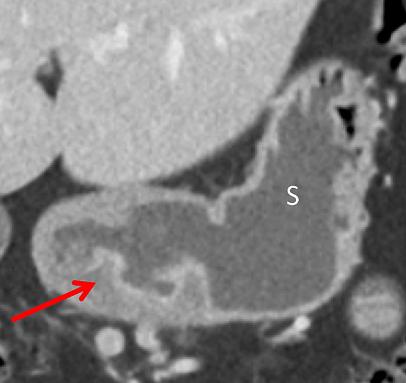

中年男性,突发恶心、呕吐。CT 增强门脉期示胃体部胃壁稍增厚,增厚的胃壁内可见散在气体,另外肠系膜静脉积气。

老年男性,气肿性胃炎,上腹部疼痛。CT 平扫示胃壁积气,腹腔及门静脉积气。